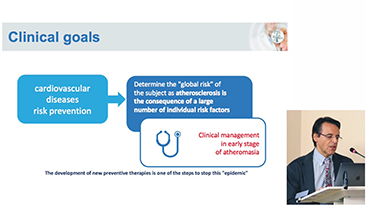

Aparaty ultrasonograficzne z serii Resona, dzi?ki szerokiej gamie za pomoc? wszechstronnych sond do r√≥?nych zastosowaŇĄ i wydajnych narz?dzi do zastosowaŇĄ klinicznych, pomagaj? U?ytkownikom stawia? dok?adniejsz? i efektywniejsz? diagnoz? oraz ocenia? wyniki.

Wspó?czesna rzeczywisto?? medyczna jest bardzo wymagaj?ca. Nieustannie wzrasta liczba trudnych przypadków i nak?adów pracy.